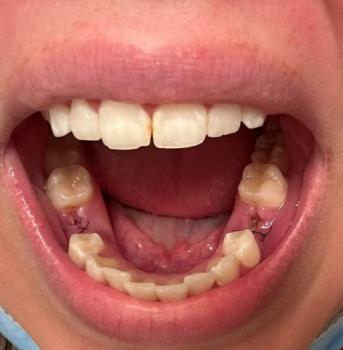

The image shows a blackened area on a back tooth, with swelling of the surrounding gum tissue. The dark spot on the tooth suggests advanced tooth decay, while the raised and irritated gum indicates a localized gum abscess or infection. This combination often causes bad taste or foul odor due to bacterial activity.

This condition usually develops when decay reaches deeper parts of the tooth and spreads toward the gum.

This case shows advanced tooth decay with gum abscess, a clear sign of active infection. Prompt dental treatment is essential to stop infection spread and preserve oral health.